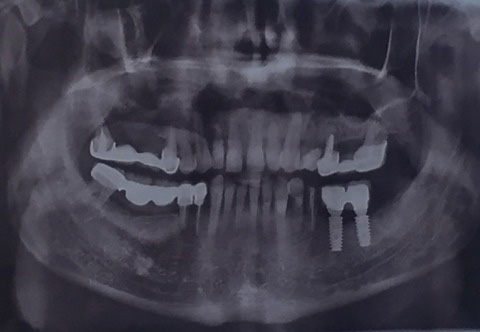

26-ого октября в учебном центре Стом-Лайн был проведен мастер-класс на тему «Закрытый и открытый синус-лифтинг при имплантации, с использованием имплантатов Thommen Medical». Мастер-класс провел главный врач-стоматолог клиники «Нюанс» в Москве Мхитар Казарян.

Мастер-класс начался с представления швейцарских имплантатов Thommen Medical, официальным предтсвителем которых является клиника Стом-Лайн. Далее были проведены обсуждения предстоящей операции и исследования компьютерной томографии, после чего участники смогли присутствовать на операции или следить за ней из учебного центра.

Во время операции доктор Казарян представил на практике особенности и преимущества имплантатов Thommen Medical.